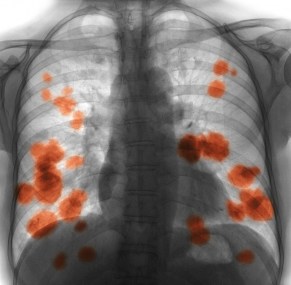

Lung squamous cell carcinoma is the second-most common subtype of lung cancer and accounts for around 30 per cent of all lung cancer cases.

One of the reasons why lung cancer is so deadly is that by the time the cancer is discovered, often due to the way it mimics other lung diseases, it is already in an advanced stage and often inoperable.